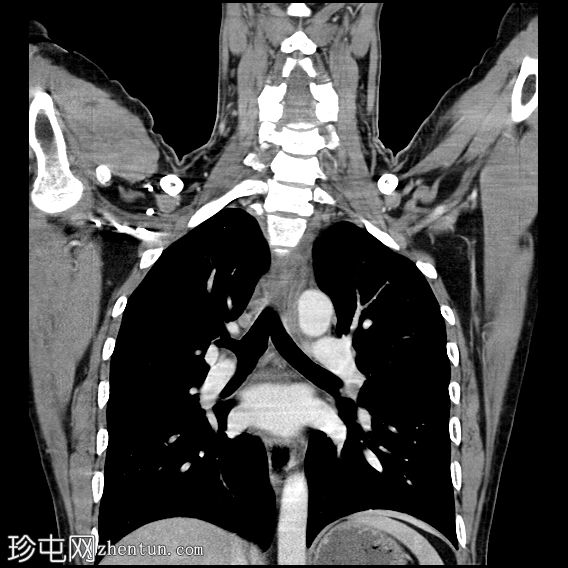

冠状位增强扫描(门静脉期)

颈段食管内可见一线状水平方向的高密度异物。

颈段和上胸段食管可见长段环周强化壁增厚,符合异物嵌顿引起的反应性水肿改变。

可见食管壁撕裂,可能与异物的方向有关。此外,可见多个食管周围气腔,提示可能存在食管穿孔。

未见纵隔积气、食管周围脓肿或明显穿孔的证据。